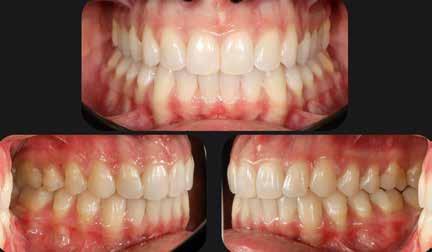

Általánosan elmondhatjuk, hogy a fogszabályozó kezelés iránt érdeklődő páciensek az első konzultáció során elsősorban az esztétikai kívánalmaiknak adnak hangot, és ritka az olyan eset, amikor a funkcionális problémák kerülnek előtérbe a részükről.

Nagyon fontos, hogy a modern arc- és mosolyesztétika által vezérelt fogszabályozási elvek alkalmazásával – minden esetben – az esztétikai céloknak megfelelően kerüljön megvalósításra az okklúziós korrekció.

A 28 éves hölgypáciens is elsősorban a szép mosoly elérésének igénye miatt szeretett volna fogszabályozást, bár tudomása volt a mélyharapásáról (1–5. képek).

A kezelési célokat a fogívek tágítása a megfelelő mosolyszélességhez és az alsó frontfogak torlódásának feloldásához, valamint a mélyharapás és a kismértékű disztálharapás korrekciója jelentették (6–11. képek).

Passzív önligírozó fix fogszabá-

lyozó készülékkel 15 hónapig tartott a kezelése. Az ilyen mélyharapásos esetekben nagyon fontos, hogy a harapásemelésnél nem történik intrúzió a felső fogíven, mert az kifejezetten negatívan befolyásolná a vertikális mosoly-display-t! A fogszabályozó kezelés után, ahogy az általában lenni szokott, a bölcsességfogak eltávolításra kerültek. Mint minden esetben, a fogszabályozás aktív fázisa után a retenció, a passzív helyben tartó fázis a kezelési eredmény megtartásához rendkívül fontos!